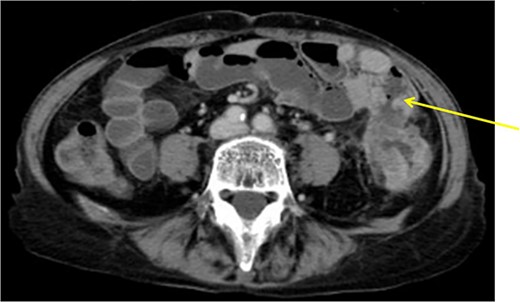

The patient was a 65-year-old man presenting to our hospital with complications of diarrhea for a year and weight loss. Colonoscopy showed rectal cancer on the anal verge (13 cm) with circumferential stenosis. Laboratory findings showed that the serum carcinoembryonic antigen (CEA) level was 4.7 μg/ml and that the serum carbohydrate antigen 19-9 (CA19-9) was 72.2 U/ml. A computed tomography (CT) scan of the abdomen showed thickening of the rectal wall with inflammation. Fistula formation between the ileum and the rectum was observed. Enlarged lymph nodes were also noted around the rectum and no enlarged mesenteric lymph nodes (Fig. 1). The patient was diagnosed with rectal cancer with ileum invasion and then scheduled to undergo surgery. We performed single-incision laparoscopic low anterior resection of the rectum with D3 dissection and partial resection of the ileum. Lymph node dissection, including the area of the inflow vessel, was also performed due to observed lymph node swelling in the mesentery of the ileum around the fistula formation intraoperatively. The operative time was 326 min, and the blood loss volume was 15 ml. Histopathological analysis revealed that the lymph nodes in the small intestine were positive for metastasis, and the diagnosis was pT4b (small intestine) N1 (2/16 (#251, 1/12, #252 1/4, #253 0/0)) M1 (small intestine mesenteric lymph node (1/1)), nonsolid type (por2) adenocarcinoma, ly3, v2 f Stage IV [TNM (tumor, nodes, metastasis) classification] (Fig. 2a and b). After discharge from the hospital, capecitabine plus oxaliplatin was administered for 6 months as adjuvant chemotherapy. The patient has been recurrence-free for 2 years after surgery.

Fistula formation between the small intestine and the rectum was observed. Enlarged lymph nodes were also noted around the rectum.